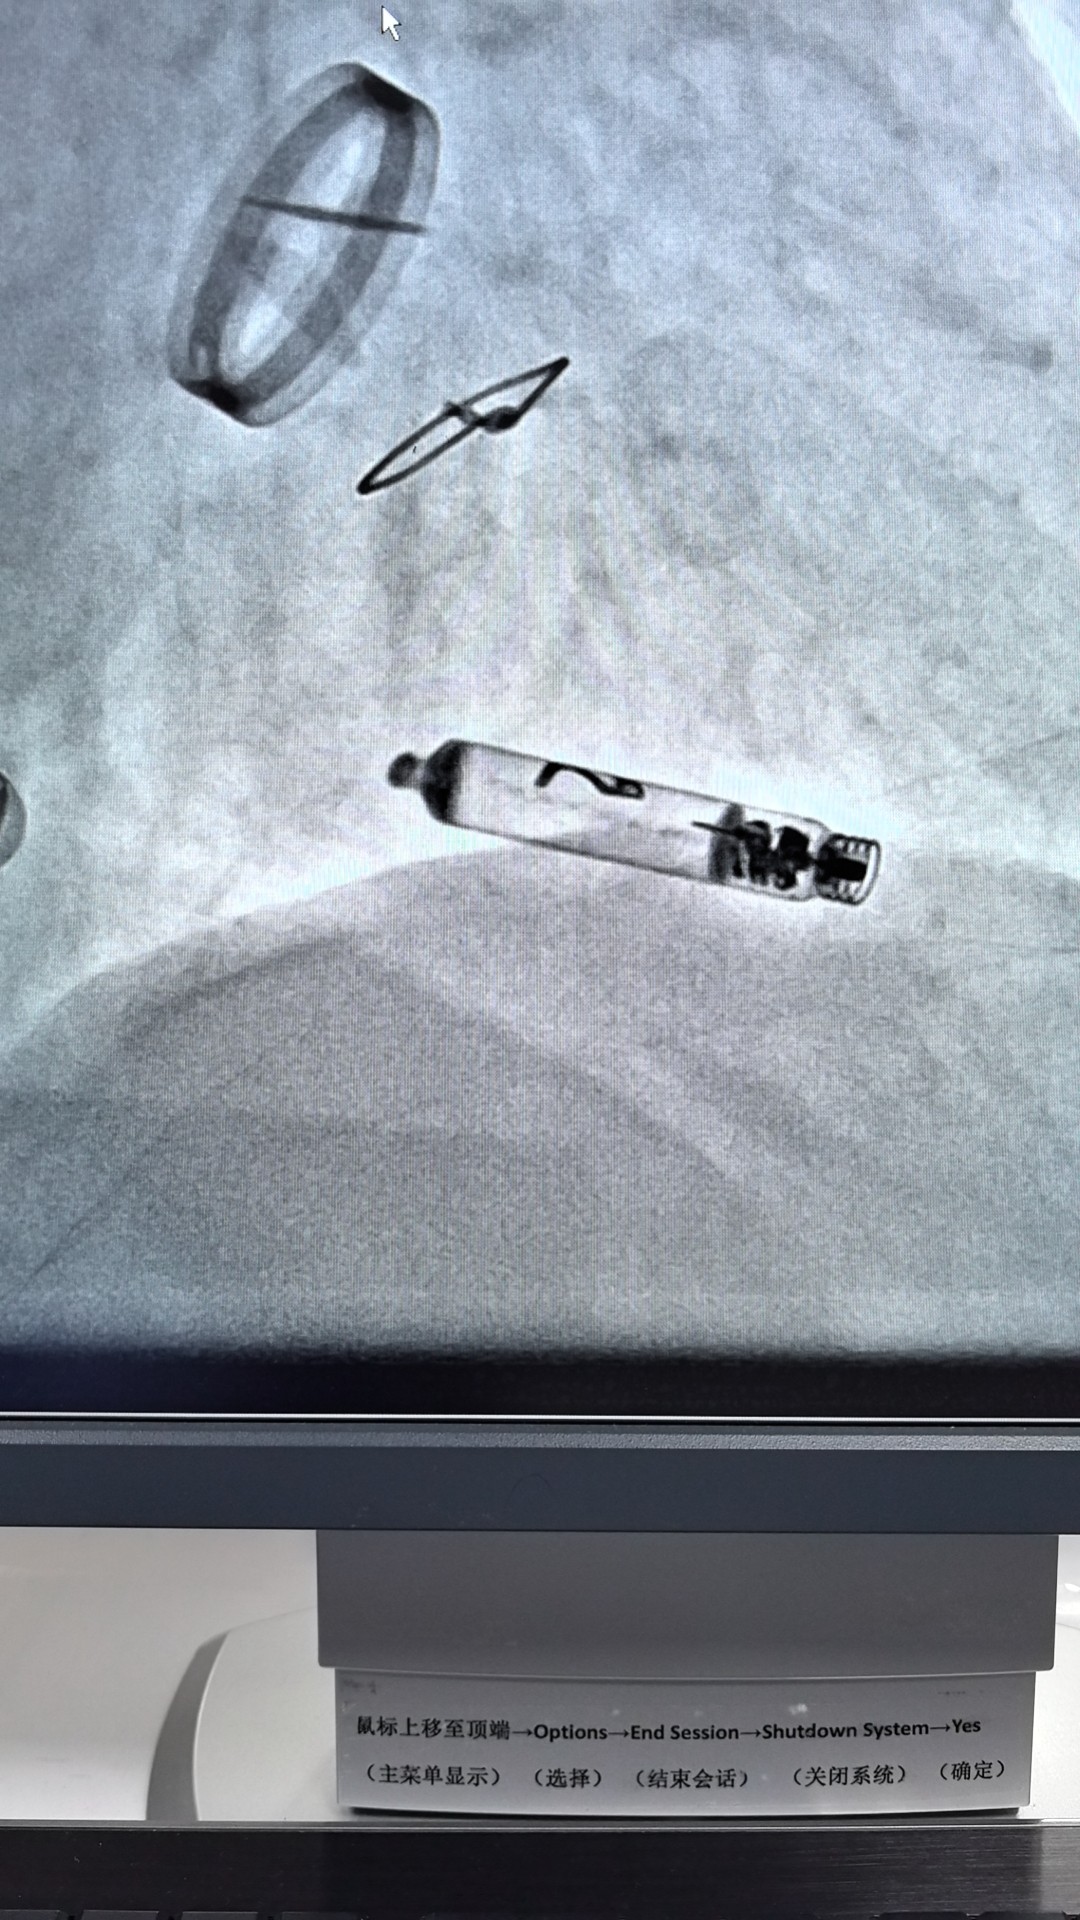

面对这一治疗难题,心血管内科一病区邓英松副主任医师团队决定采用前沿的雅培Aveir VR无导线起搏技术。该技术核心优势在于其微创性和安全性:起搏器仅重2.4克,形似胶囊,通过股静脉穿刺,经导管精准输送至右心室间隔部植入。

手术无需切开皮肤制作囊袋,也无需植入心内膜导线,从根本上规避了囊袋出血和感染风险。特别值得一提的是,该起搏器是全球唯一具备实时心内电信号标测技术的无导线起搏器,医生可在释放前精确定位最佳起搏点(莫女士手术中测得阈值0.5V@0.4ms),显著提升手术精准度和长期效果。此外,其独特的螺旋电极可主动旋入心肌固定,并具备未来可安全取出的设计。